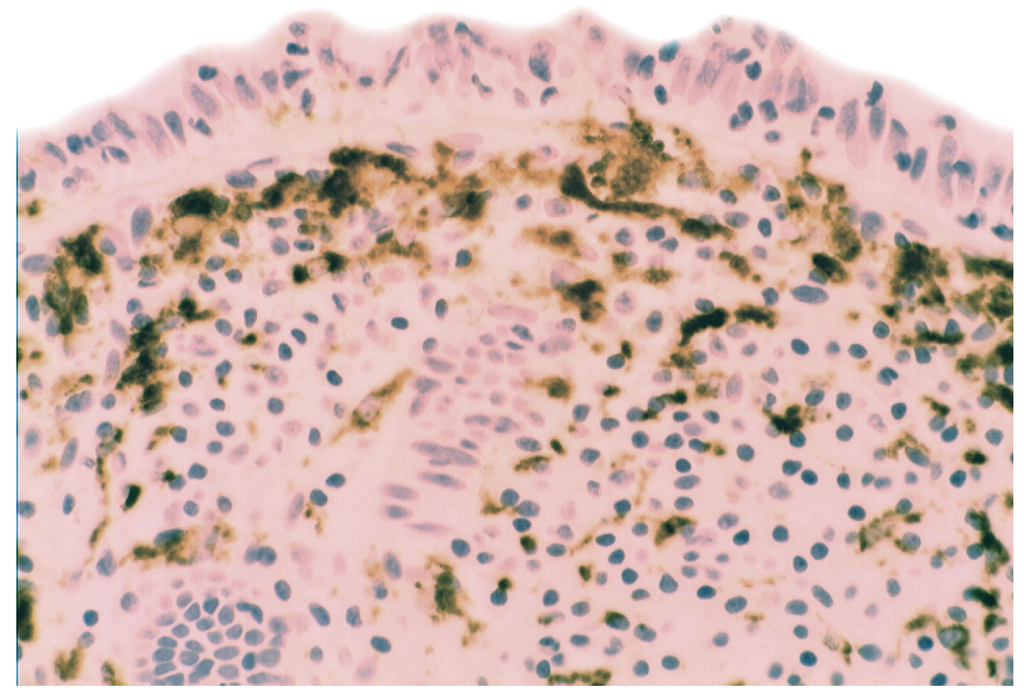

In collagenous colitis lysozyme is up-regulated in the colonic crypts and in metaplastic Paneth cells [9] (Figure 11). In lymphocytic colitis, lysozyme is up-regulated in macrophages underlying the surface epithelium of the lamina propria [9] (Figure 12), as well as in the lower part of the crypts (Figure 13).

Figure 13.

Lymphocyic colitis showing lysozyme expression, in the basal aspect of the crypts (arrow, lysozyme immunostain, ×20).